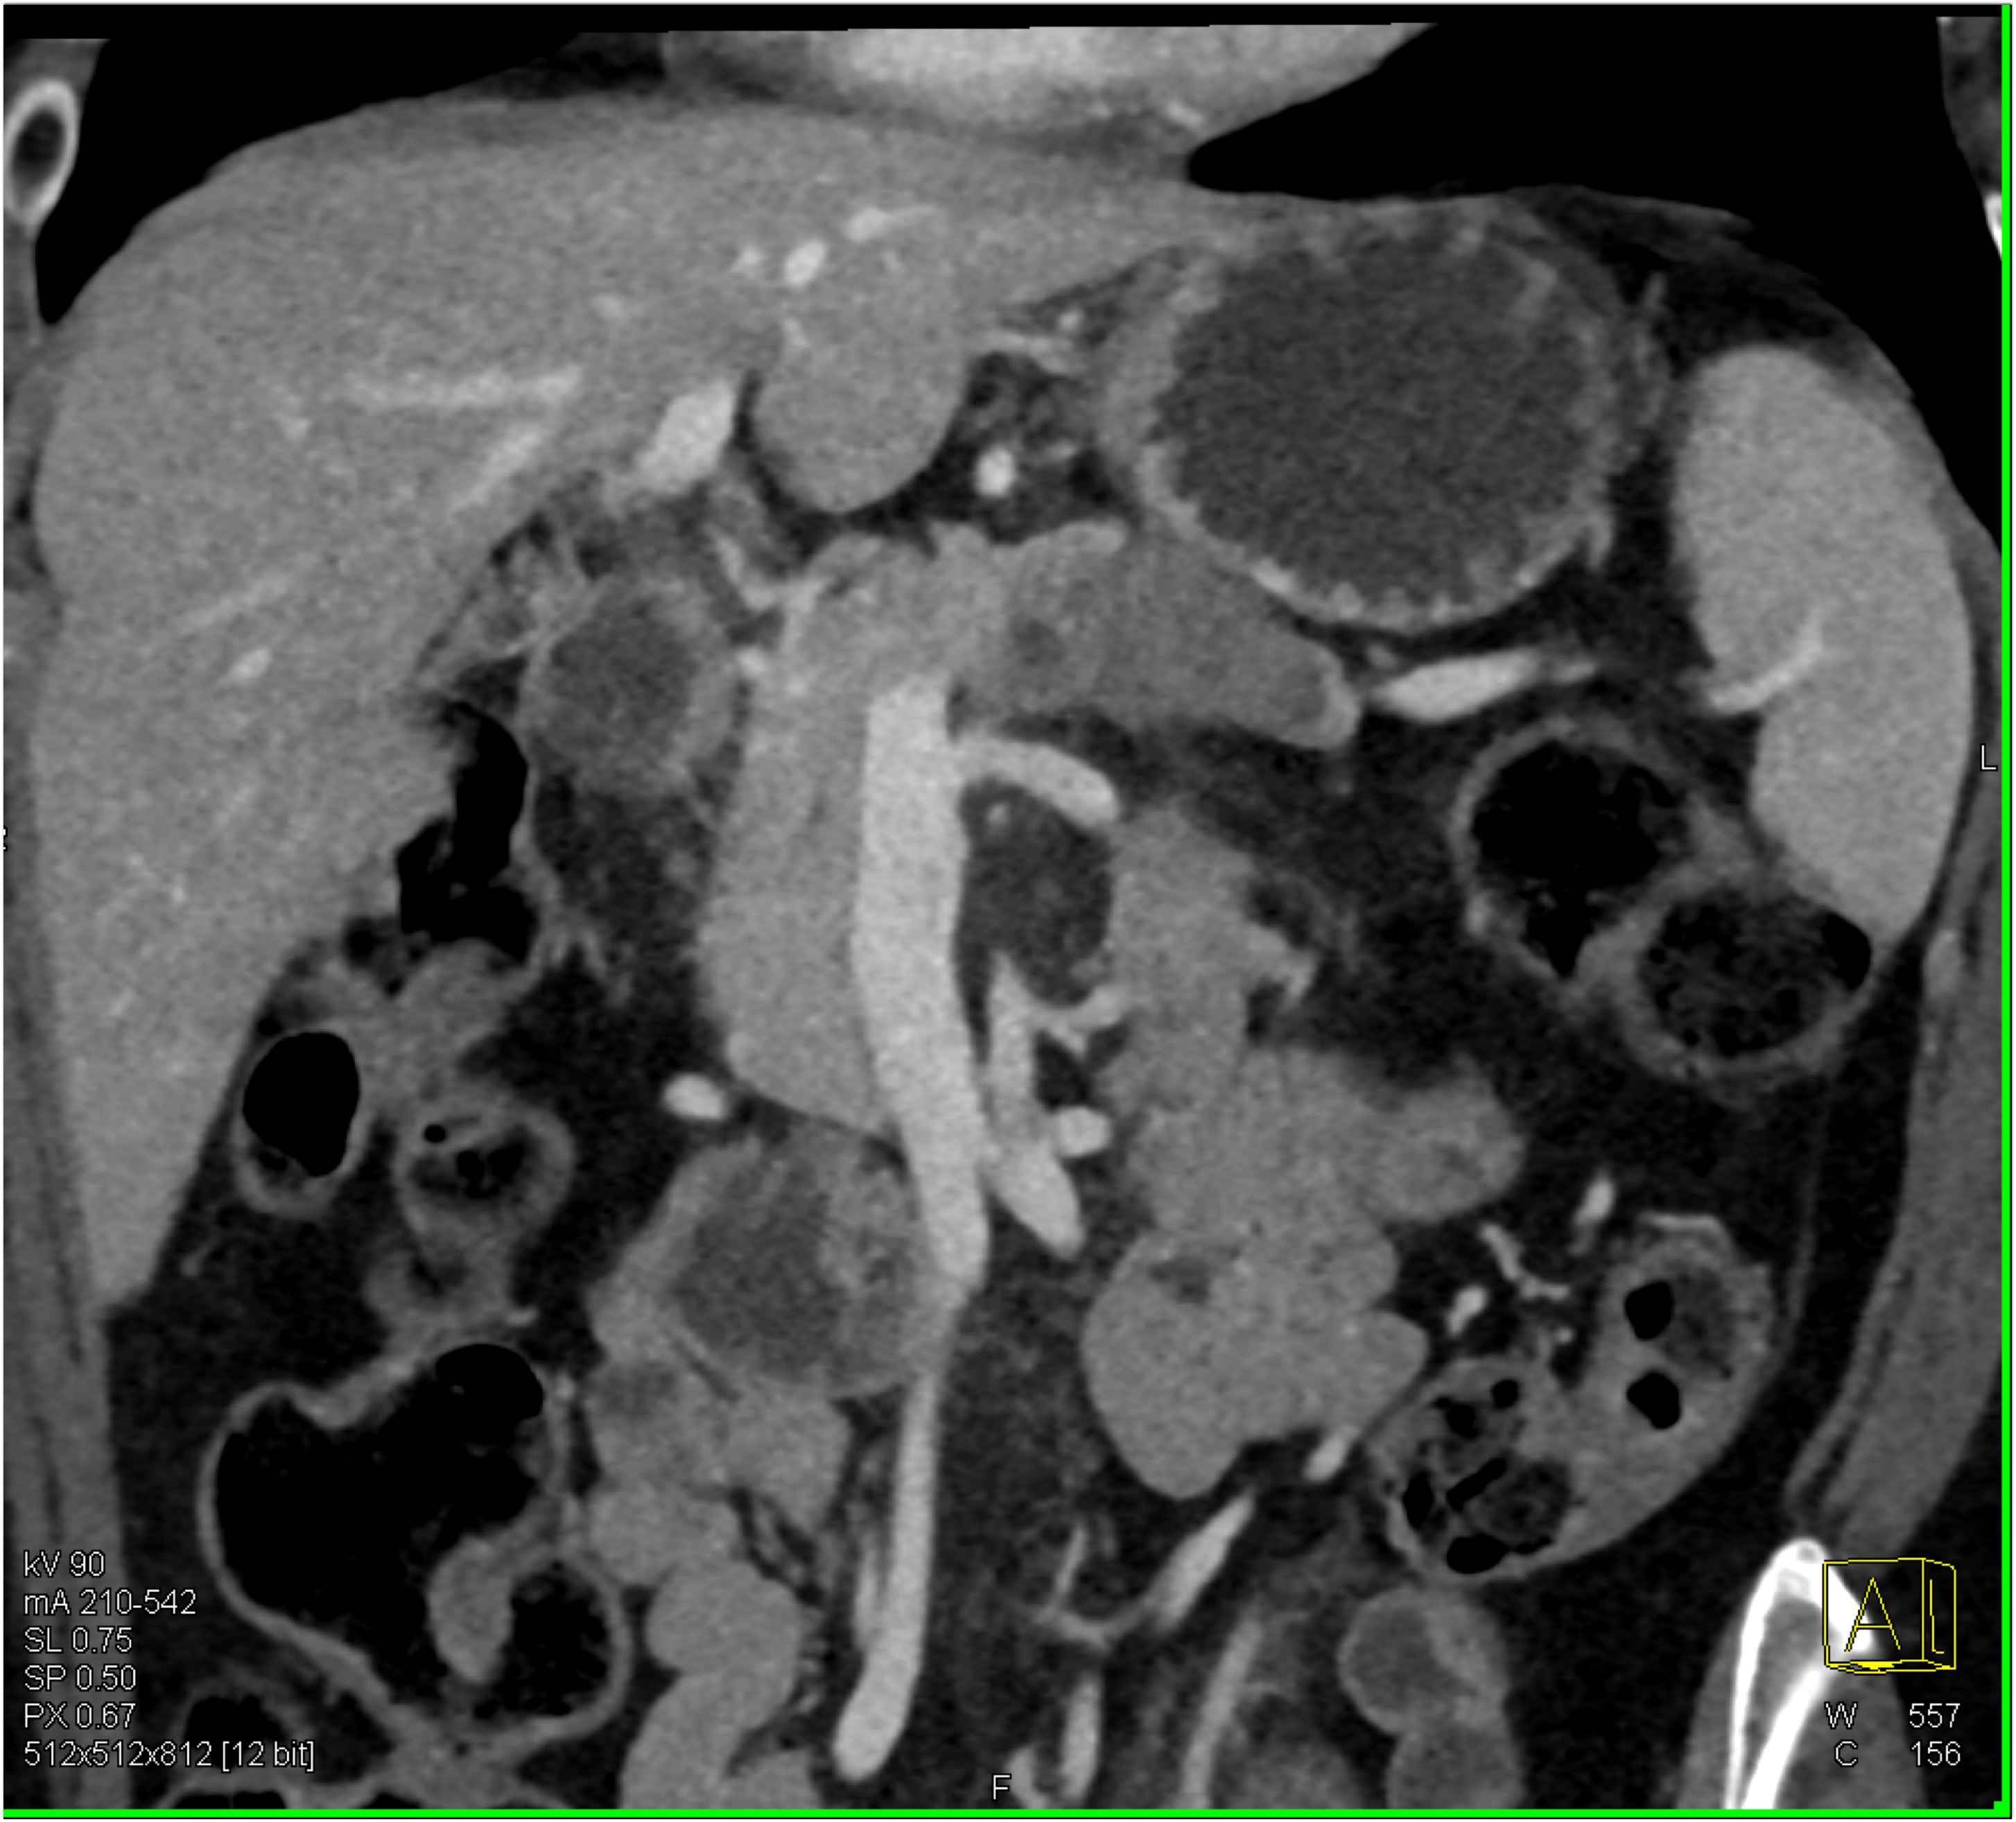

2) In this patient on dialysis for ESRD the best diagnosis is?

normal bypass graft

AV fistulae with aneurysms

vasculitis

infectious vascular disease